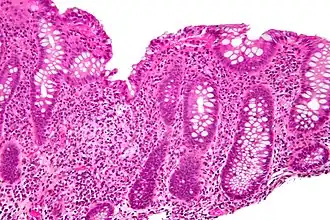

Cryptitis. H&E stain.

Cryptitis. H&E stain. -